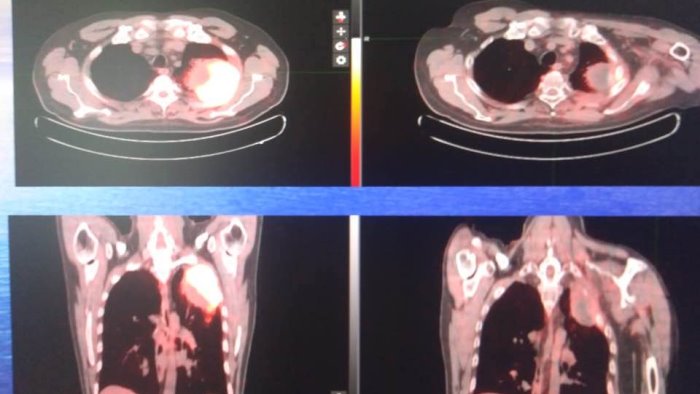

"Ad oggi, - dichiara il dottore Di Gennaro - , sono più di 20 i pazienti trattati, ed i risultati sono al di là delle nostre aspettative, anche su coloro ai quali, effettuavamo una radioterapia palliativa o compassionevole. Questa tecnica è adoperata per neoplasie resistenti e dal volume molto grande, con diametri al di sopra dei cinque centimetri, continua Di Gennaro, e abbiamo potuto notare, esaminando in particolar modo, dal 2022, un paziente con un tumore di oltre 10 cm, ora toralmente in remissione, che la combinazione tra radioterapia potenziata e immunoterapia, da risultati che fanno ben sperare in una probabile guarigione". La suddetta tecnica, è stata oggetto di osservazione da parte di 5 giovani medici radioterapisti cinesi, che per 5 mesi, sono stati presenti nel Reparto di Radioterapia del Ruggi, nell'ambito del Progetto 'Cross Sciences MediCina', per imparare la procedura direttamente sul campo. "Seguendo il nostro esempio - spiega infatti il Dottore Di Gennaro - dopo tre mesi dal loro rientro in Cina, ed ispirandosi alla nostra esperienza, i medici osservatori, hanno irradiato 46 pazienti e cio' ci gratifica e ci rende orgogliosi di aver portato la nostra innovazione nel settore medico sanitario, in un Paese lontano e culturalmente cosi diverso, che ci guarda con ammirazione e con intenti collaborativi'.